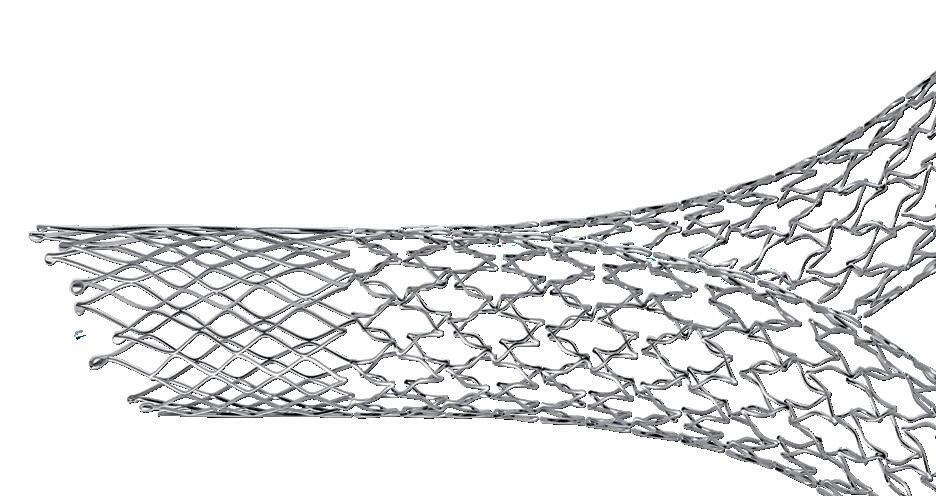

In the ongoing endovascular era, Thompson put forward, several innovations—including bioresorbable stents and non-invasive devices—have refined, or are set to refine, longstanding techniques and technologies. Indeed, the presenter said, there is “still room” for endovascular innovation despite the largely unchanging nature of its fundamental building blocks. However, these innovations will not, in Thompson’s view, ‘change everything’ in vascular surgery. Instead, he argued that the next paradigm shift in the field will be defined by the accelerated pace of technological change that is happening in the wider world.